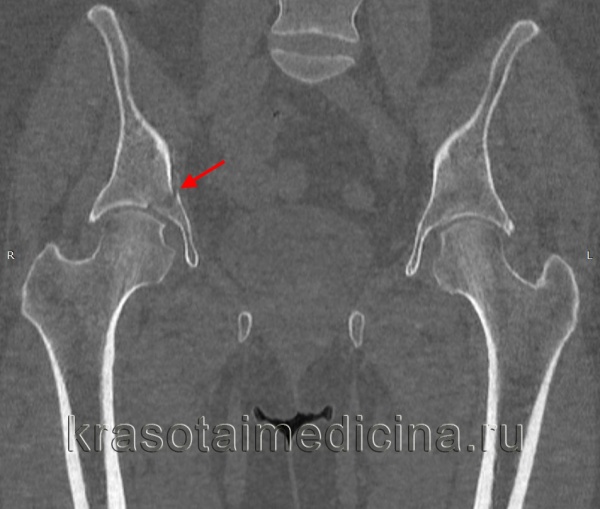

При поступлении пациента с травмой вертлужной впадины наличие у него вывиха в тазобедренном суставе являлось показанием к его экстренному вправлению с последующим наложением скелетного вытяжения или аппаратной фиксацией. Это является залогом успеха последующей реконструкции. Так, на рисунке 1 слева представлена рентгенограмма пациента с переломом задней колонны левой вертлужной впадины со смещением и вывихом бедра. Вправление вывиха бедра в экстренном порядке привело к репозиции перелома задней колонны вертлужной впадины (рис. 1 справа), что в дальнейшем облегчило выполнение остеосинтеза.

Рисунок 1. Рентгенограммы мужчины 32 лет. Автодорожная травма (удар в область левого колена при столкновении): слева – при поступлении, перелом задней колонны левой вертлужной впадины со смещением, вывих левого бедра; стрелка указывает на смещение фрагмента задней колонны; справа – после вправления вывиха в экстренном порядке наступила репозиция перелома; стрелка указывает отсутствие смещения